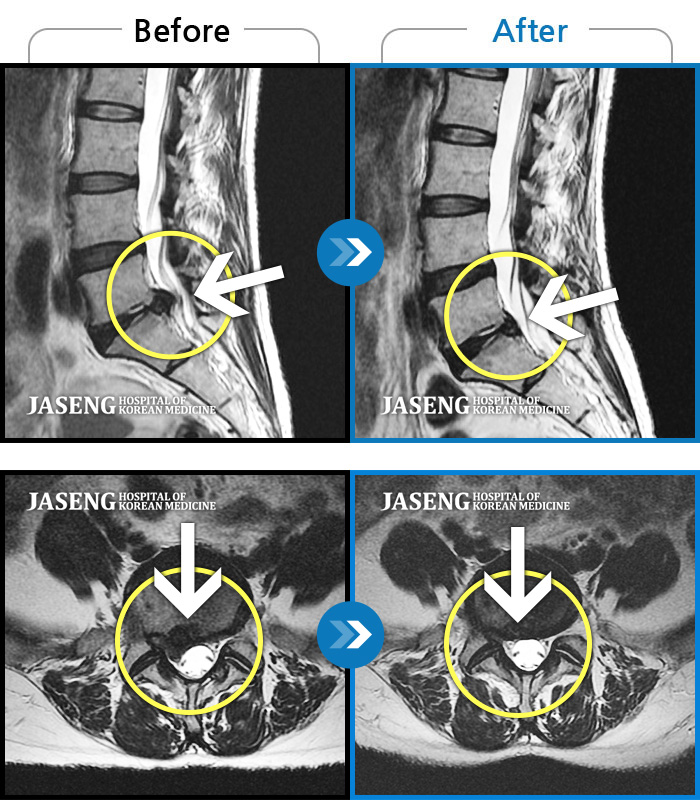

Before

After

환자에게 사전 동의를 받아 동일 조건에서 촬영되었습니다.

개인에 따라 치료 후 부작용이 발생할 수 있으니 의료진과 상담 후 치료를 진행하시기 바랍니다.

허리굽히는 동작을 한 후 우측 골반통증 및 우측 하지외측 저림, 근력저하가 있었다.

허리와 골반이 아프고, 좌측 다리에 통증과 저림이 있었다.